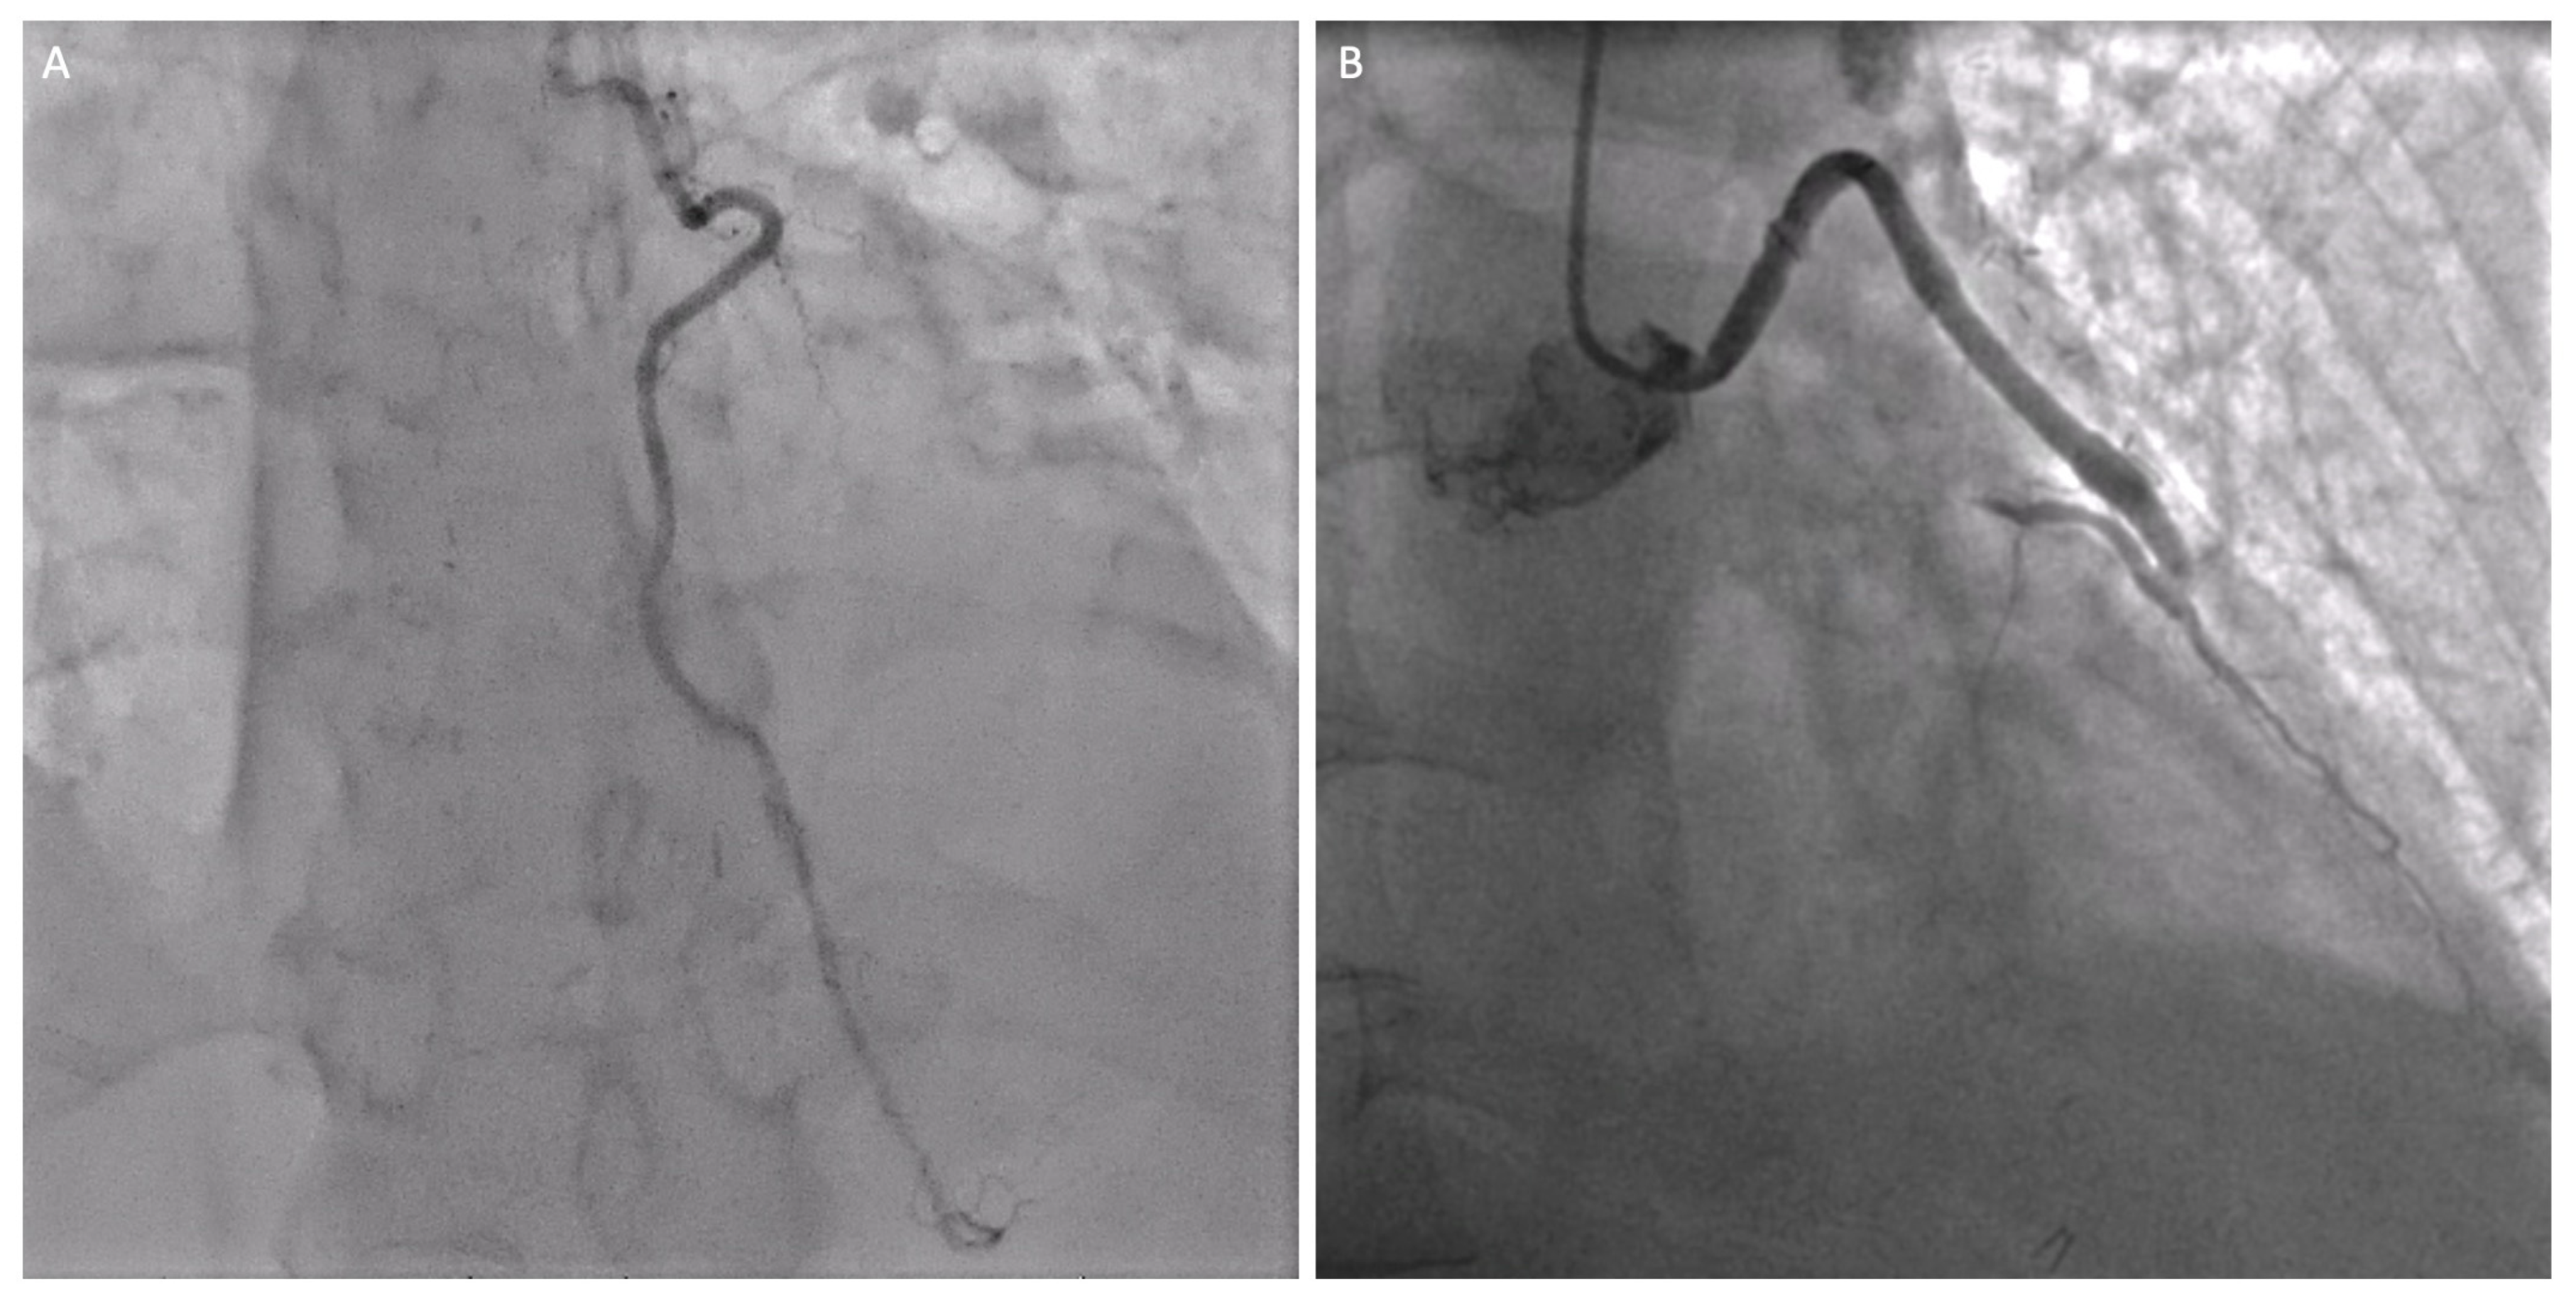

- Absence of calcification of the ascending aorta, allowing the execution of the proximal anastomosis (Figure 4A).